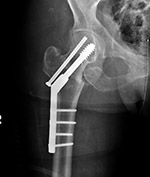

A special type of screw used in the treatment

of intertrochanteric proximal femur fractures

is called a dynamic compression screw (device) consisting of a large lag screw with

distal threads that is inserted into the femoral

head and neck. This screw fits into the barrel of a

side plate, which is secured to the femoral shaft

with multiple cortical screws. The lag screw can

slide within the barrel, which results in compression

of the fracture site as the patient ambulates (figure: hip dynamic compression screw)

(Ruedi, 2007; Benjamin, 1994; Berquist, 1995; Freiberg, 2001; Hunter, 2001). If the fracture settles, the lag screw slides within the barrel preventing the screw from piercing the femoral head and entering the hip joint space.

Hip dynamic compression screw set |

1- lag screw; 2-compression screw; 3-barrel and side plate. From Benjamin, 1994 |

| Dynamic compression hip screw |

Dynamic compression hip screw, partially threaded cannulated cancellous fixation screw and washer |

Dynamic compression hip screw

|

| There is also a partially threaded cannulated cancellous fixation screw. |